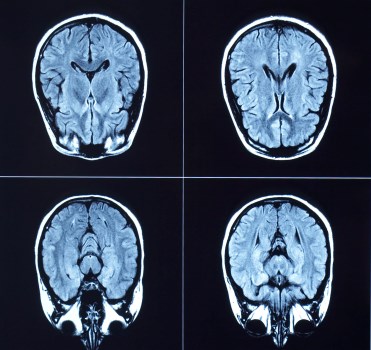

brain MRIA clot-busting drug developed to treat heart attack is now being used as a standard treatment for acute ischemic stroke, thanks in large part to research at The Ottawa Hospital.